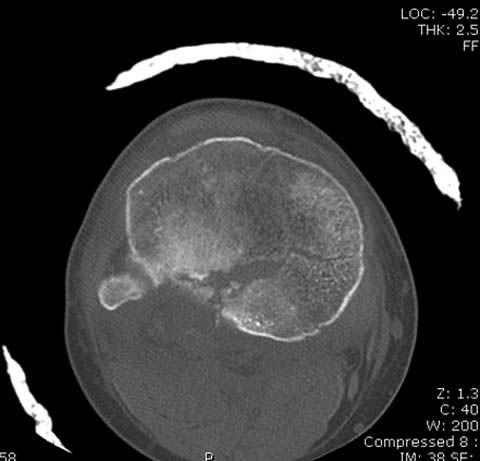

Пациенту сделали КТ - ухитрились сделать на шине Белера (не давал положить прямую ногу) - срезали передний отдел. Планируется на пятницу (24.12) на операцию - синтез длинной мыщелковой LCP-пластиной Synthes :). Отек ближе к слову умеренный (окружность голени +4 см по сравнению со здоровой). КТ и снимок на вытяжении прилагаются.

Здесь как раз тот случай, когда результат зависит не только от мастерства хирурга, но и от наличия современных методов исследования. Например, КТ которая поможет рассчитать направления шурупов и установку импланта. Кроме этого, поможет определиться с доступом.

На представленных предоперационных срезах КТ огромный задне-медиальный фрагмент расположен больше кзади, чем медиально. Для планирования, кроме поперечных срезов, надо ориентироваться на корональные срезы, которые укажут топографию верхушки медиального фрагмента.